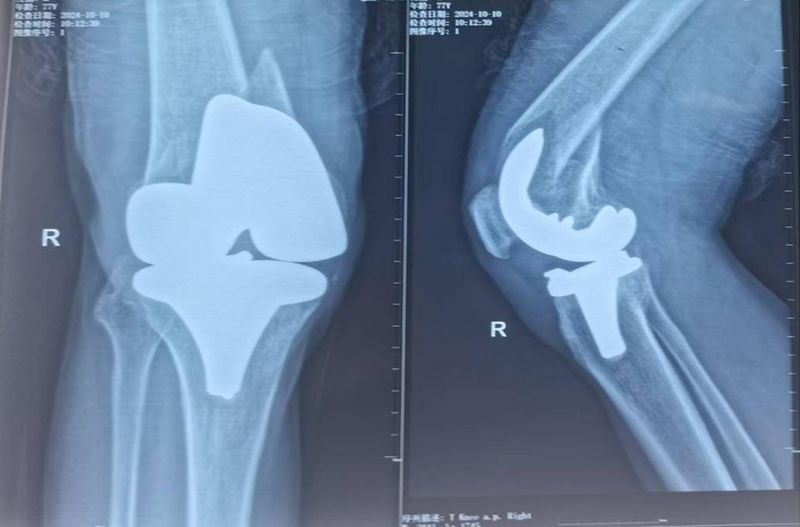

膝关节置换术后假体周围骨折,假体松动

入院后,脊柱外科许立新主任迅速组织团队对陈大爷的病情进行全面评估和针对性分析,考虑到陈大爷已是77岁高龄,且有膝关节置换手术史,假体周围骨折且假体明显松动,手术治疗将会是个巨大挑战,因为单纯的复位内固定可能无法解决假体松动的问题,甚至会导致膝关节失能,把残腿治废。在几次细致、严谨的讨论后,许立新主任团队决定为陈大爷实施膝关节置换假体周围骨折翻修手术。